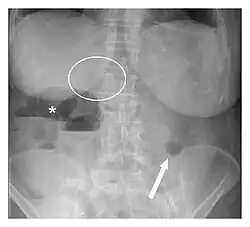

| Plain abdominal radiograph showing Rigler's triad (pneumobilia indicated by the circle, ectopic gallstone indicated by the arrow, and bowel distension indicated by the asterisk). | |

Rigler's triad is a combination of findings on an abdominal radiograph of people with gallstone ileus, a condition where a large gallstone causes bowel obstruction. Rigler's triad consists of: (1) small bowel obstruction, (2) a gallstone outside the gallbladder, and (3) air in the bile ducts.[1] It bears the name of Leo George Rigler (1896–1979), who described it in 1941.[2][3] It is not the same as Rigler's sign.

It is most commonly seen in 6th to 7th decade of life and affects females more often. Most patients with gallstone ileus are asymptomatic. Due to the fistula formation between the small intestine and gallbladder, large stones can lodge in the small bowel, leading to its obstruction. Pneumobilia means air in the biliary tract. It is due to the transfer of air from bowel through the fistula into the biliary tract.